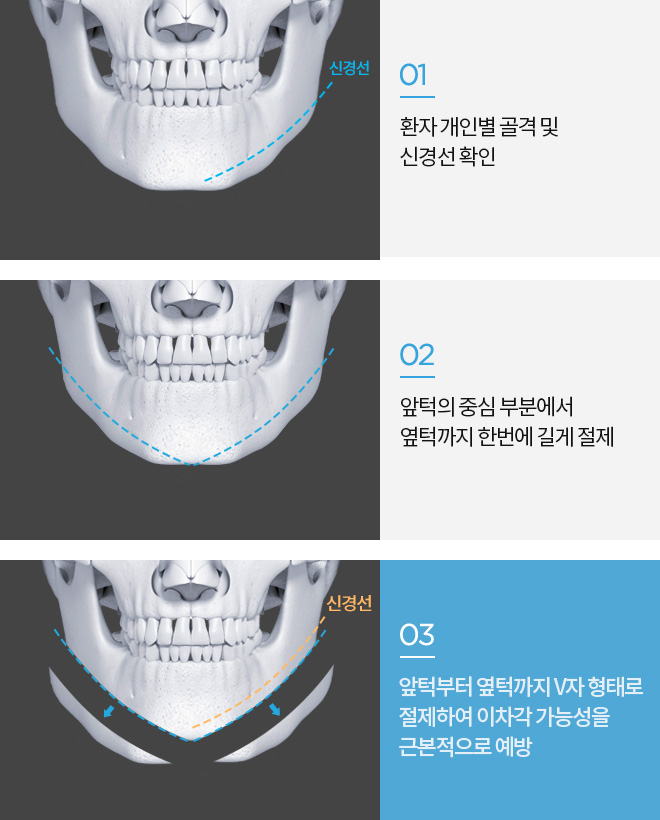

앞턱 절골 수술방법

T 절골법

ㅅ 절골법

V 절골법